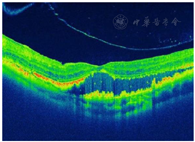

FFA检查:局灶视网膜毛细血管扩张、多发粟粒状动脉瘤及大片毛细血管无灌注区(图2)。